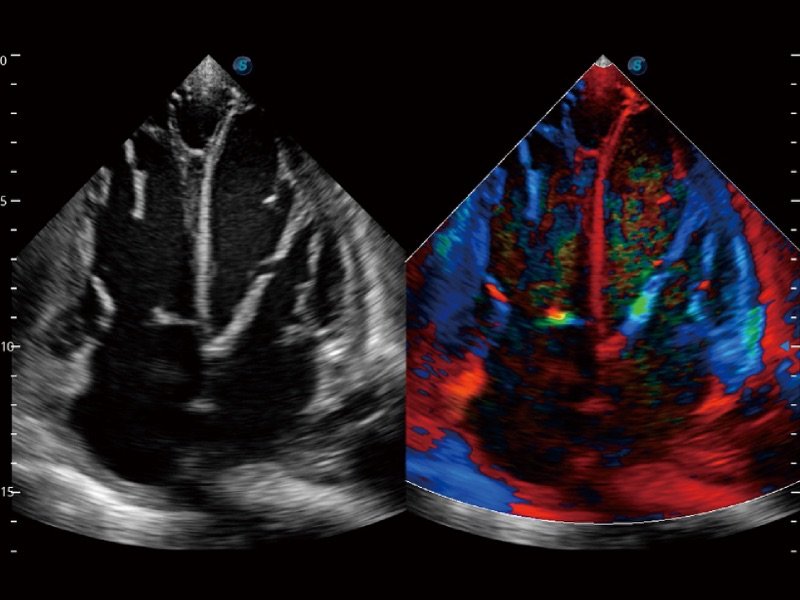

Contrast Imaging

Die Kontrastmittel sorgen für eine starke Signalreflexion, so dass schwer einsehbarer Blutfluss besser dargestellt werden kann. Regelt den Schalldruck und bietet eine vielversprechende Bildqualität bei geringerer Wirkstoffdosis.